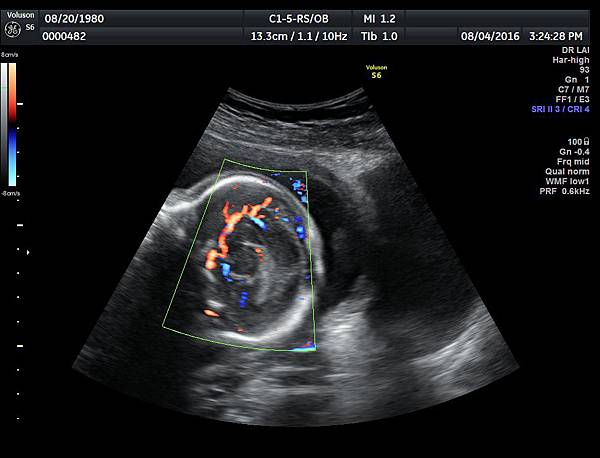

2016年8月4日在執行胎兒高層次超音波檢查時,我發現胎兒腦部的CSP(cavum septum pellucidum)很不清楚(附圖1~4),遇到這種情況,需要仔細評估胎兒腦部的駢胝體,因為CSP的天花板是駢胝體,CSP不明顯時,要合理的懷疑駢胝體沒有發育,或駢胝體下方有長東西(例如lipoma),駢胝體是連接左右大腦的神經纖維所組成。

1. 矢狀切面(sagittal plane):駢胝體呈現類似三明治的中間黑色部分,上面一層薄薄白色的區域是callosum sulcus,打上flow可以看到pericallosum artery在駢胝體上面的周圍,pericallosum artery來源是前腦動脈,參考附圖 6~10,三明治下面白白的部分是和CSP做比較得到的,如果這一層長lipoma(附圖 5),CSP很可能看不到。